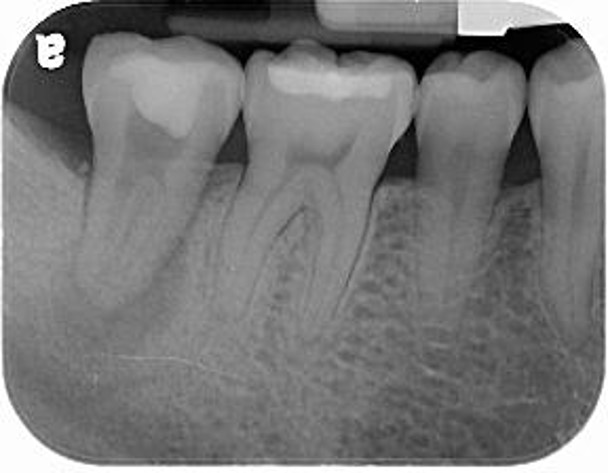

植牙前口內評估